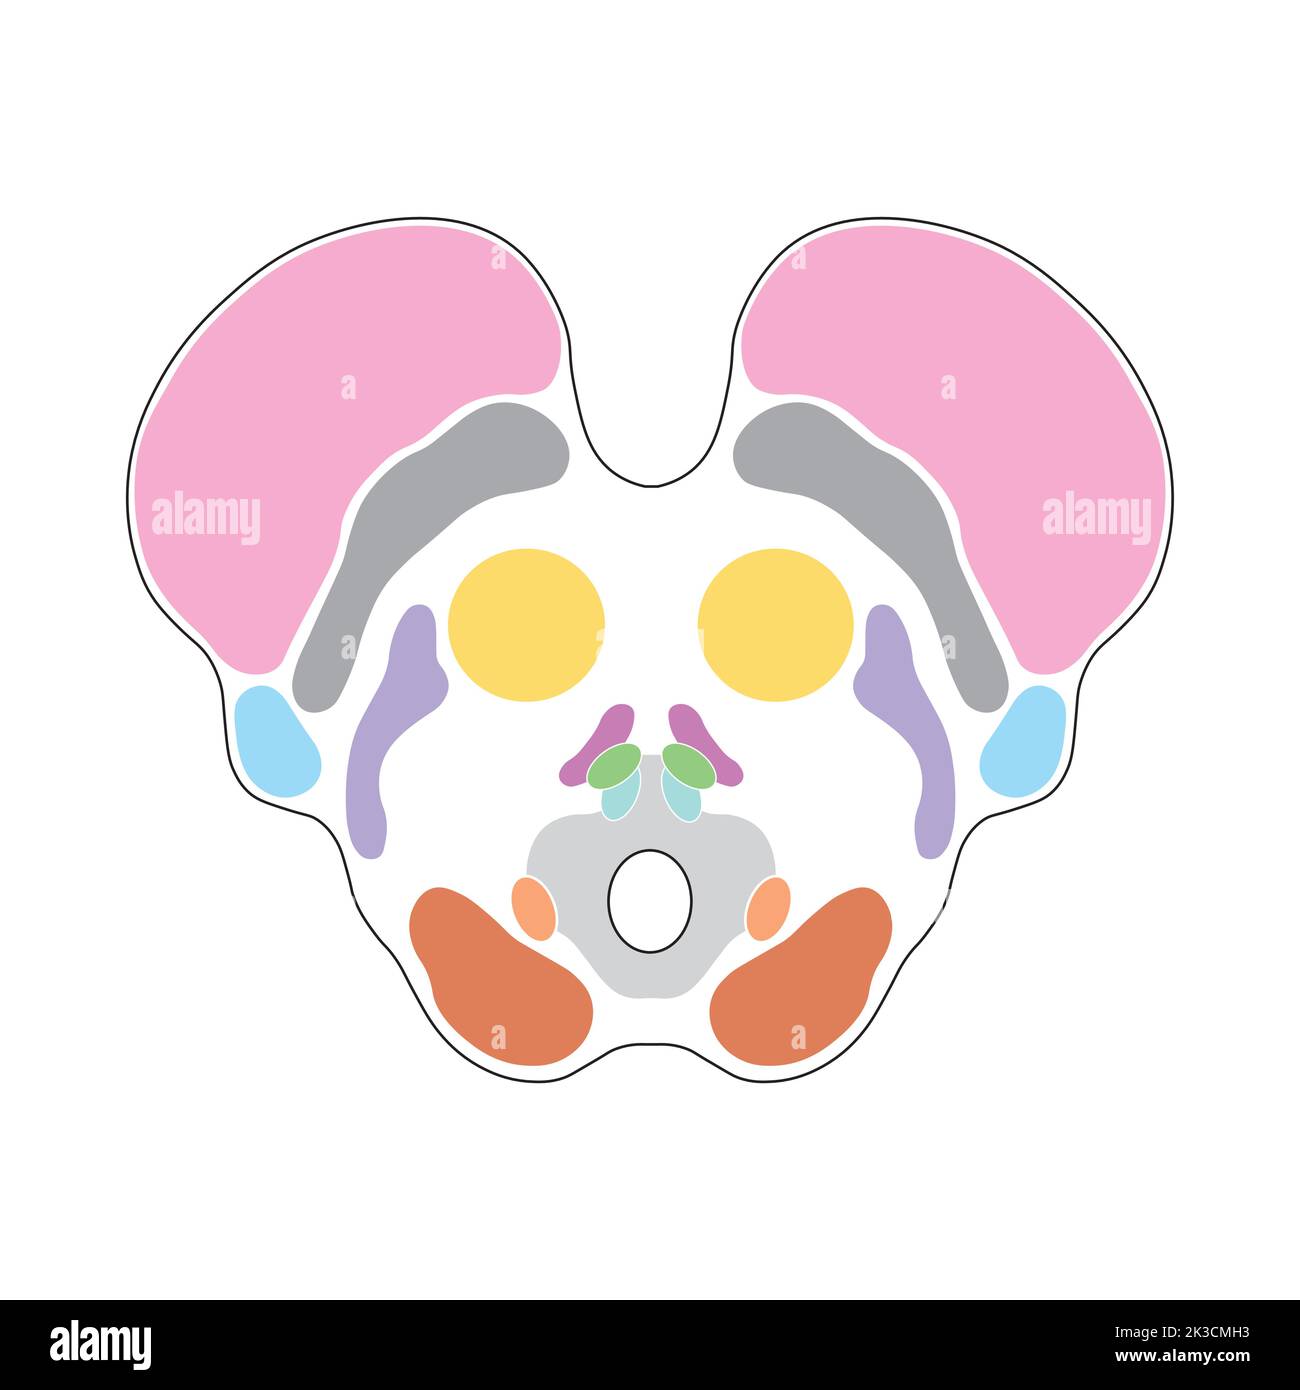

RF2XHY7B8–Anatomia cerebrale. Materia bianca e materia grigia. Corteccia cerebrale e ventricoli cerebrali con liquido cerebrospinale. Sezione trasversale di una vista frontale del cervello umano

RF2Y92GH4–Anatomia cerebrale. Vista frontale e sezione trasversale di un cervello umano. Primo piano dell'Hippocampus e dei ventricoli. Corteccia cerebrale. Illustrazione vettoriale

RF2K3CMNG–Progettazione scientifica dell'anatomia del midbrain. Sezione assiale a livello del collicolo superiore. Simboli colorati. Illustrazione vettoriale.

RF2K3CMHJ–Progettazione scientifica dell'anatomia del midbrain. Sezione assiale a livello del collicolo superiore. Simboli colorati. Illustrazione vettoriale.